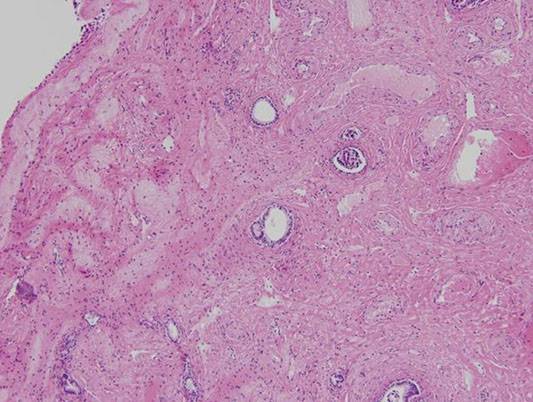

Broken into hepatic lobule (2D) or acinus (3D), where the hepatic lobule has central venule with hepatocyte cords radiating to peripheral portal tracts

Portal Tracts

Contain hepatic artery, portal vein, and bile duct

- hepatic artery is normally about the same diameter as the bile duct, and are seen together most of the time, while the portal veins have ~5x the lumen diameter

- 1/10 of the smallest branches of the portal tracts do not have a bile duct on H&E normally

-- medium and larger portal tract should always have a bile duct

Lobules

Made of cords (plates) of hepatocytes usually 2-3 cells thick

- hepatic plate thickness best seen c reticulin stain

- hepatocytes have blood flow on both sides, one from portal venous blood and other from blood from hepatic artery

- sinusoids lined by fenestrated endothelial cells

- under endothelial cells is the space of Disse, that extend into hepatocyte microvilli (space of Disse also contains fat-containing myofibroblastic hepatic stellate cells)

- Kupffer cells are scattered on the luminal surface of endothelial cells

- between hepatocytes are bile canaliculi (separated from vascular space by tight junction) that drains into canal of Hering, which then goes to bile ductules in periportal region, that empty to terminal bile ducts in the portal tracts